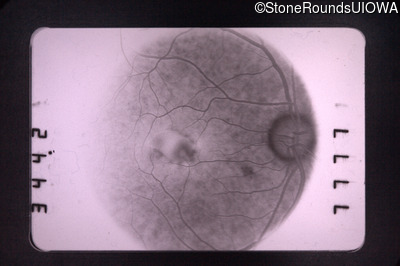

Pattern Dystrophy (IIC)

This 47 year man first experienced some decrease in his central vision about 10 years ago.

Diagnosis & molecular findings

Disease Gene Allele 1 variant(s) Allele 2 variant(s) Inheritance mode

Pattern Dystrophy PRPH2 Gly167Asp GGC>GAC   AD